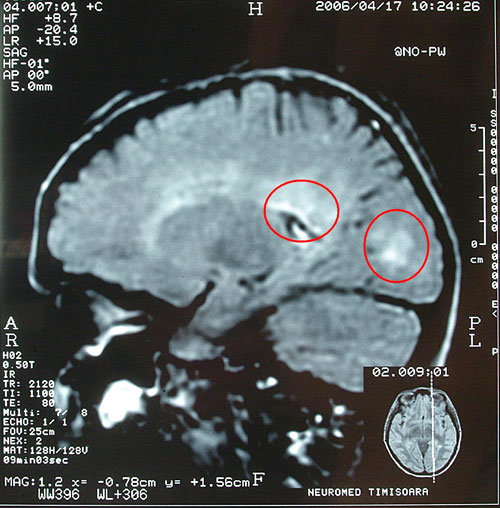

Iar rezultatele acestea în SM se observă atât prin regresia simptomelor cât și pe RMN, prin dispariția imaginilor de demielinizare.

Exemplu: imagini RMN cu placa de demielinizare (aspect de placă albă) dispărută (periventricular) și alta mult micșorată (zona occipitală) în cursul api-fito-terapiei

RMN 04.2006 (anterior api-fito-terapiei)

RMN 02.2007 (în timpul api-fito-terapiei)